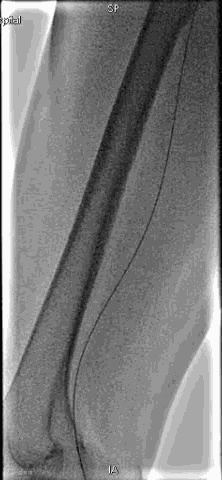

手术过程

抽吸结果